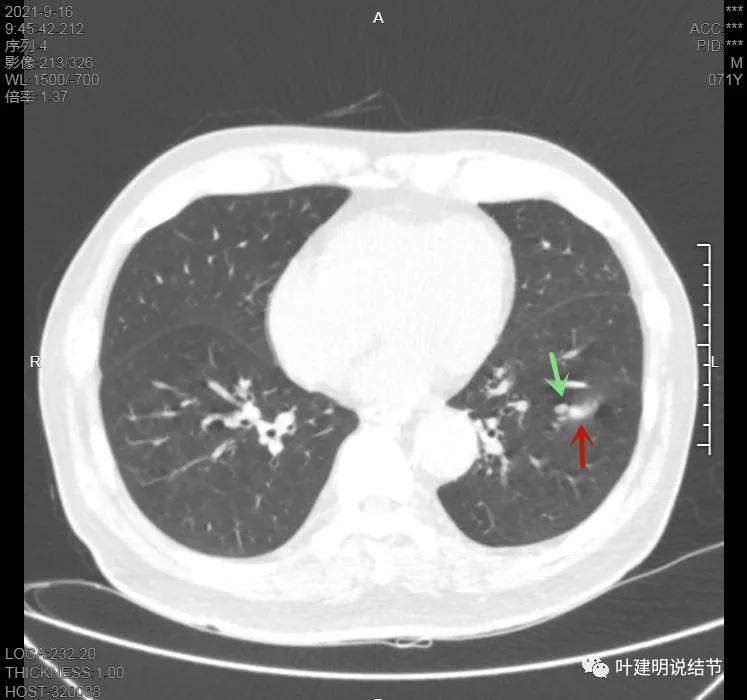

上图示病灶在左下叶,红色所指的与绿色箭头所指的是两个病灶,不相连的,实性结节

上图也示病灶是两个的,小的与大的之间有间隙的。大的病灶呈长方形似的